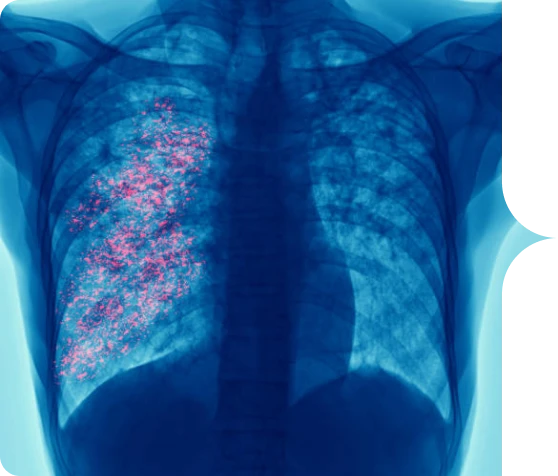

es un virus frecuente que infecta la nariz, la garganta, los pulmones y que generalmente causa síntomas leves

y similares a los de un resfriado.1,2

Algunas personas, especialmente los adultos mayores y los bebés menores de 6 meses, pueden necesitar hospitalización. El VSR puede causar bronquitis (inflamación de las vías respiratorias pequeñas en el pulmón) y neumonía (infección en los pulmones).1,2